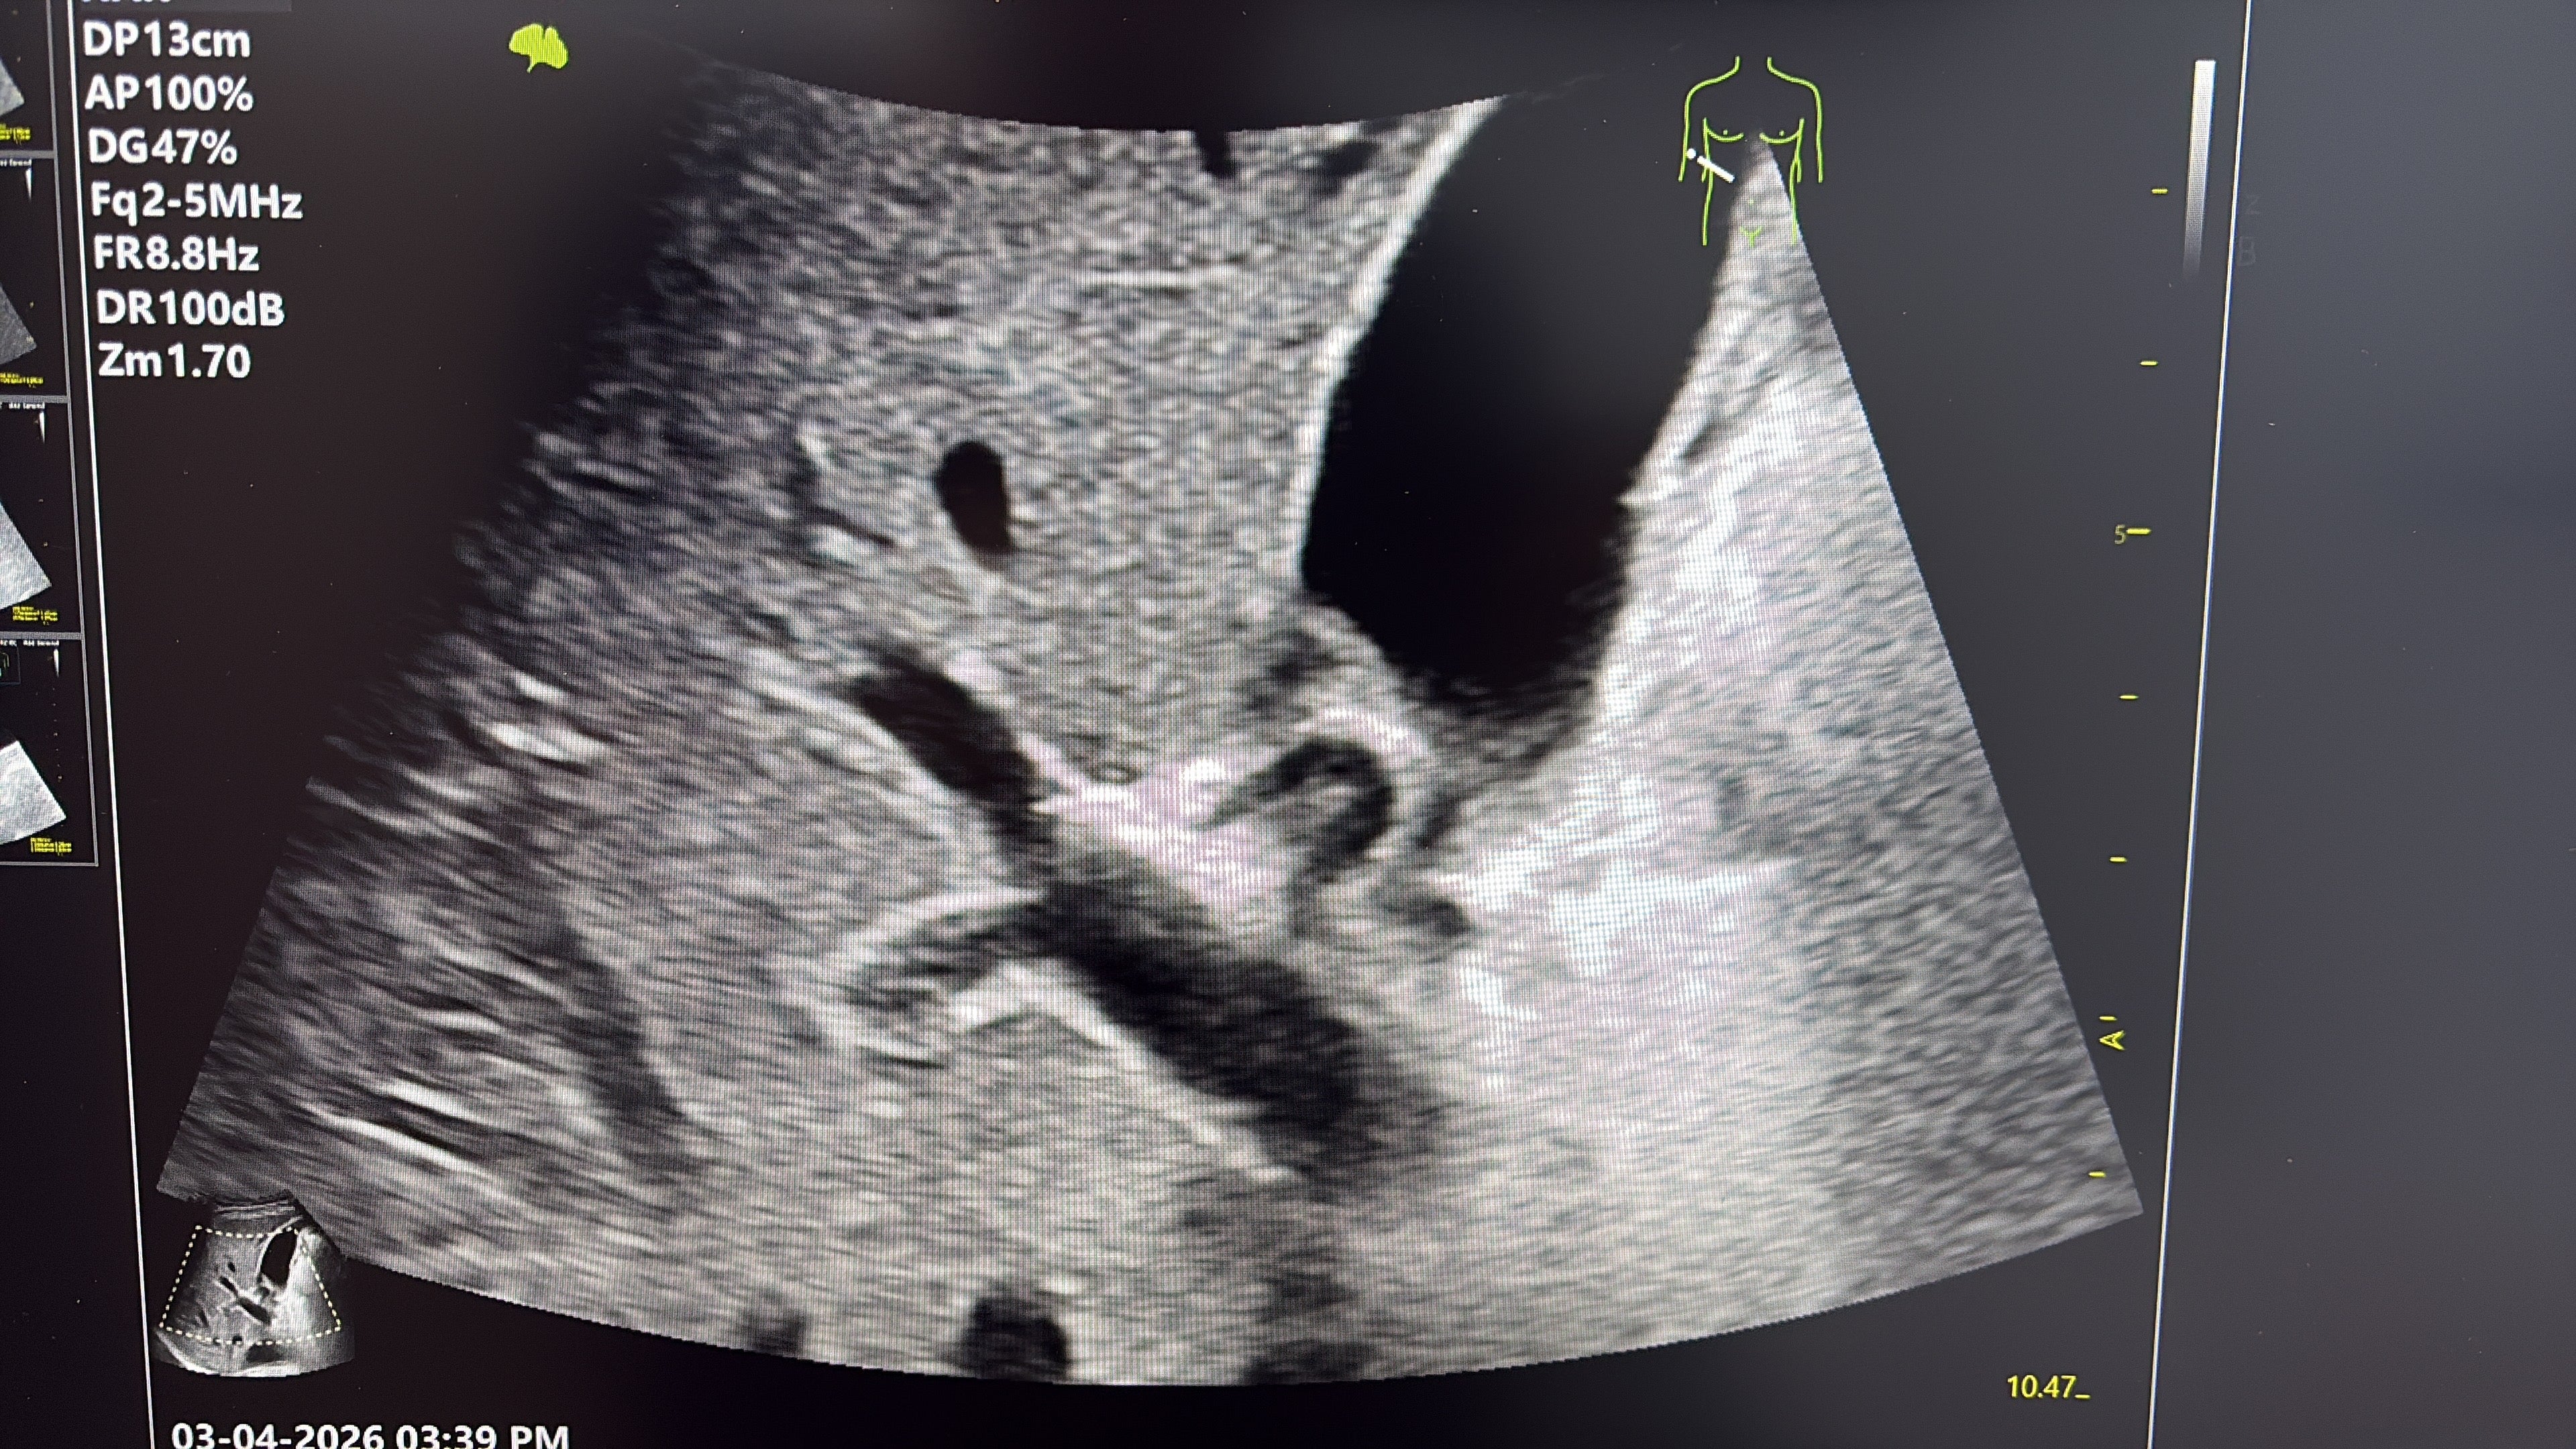

Având în vedere rezultatele imagistice, se decide prelevarea bioptică ecoghidată (3 fragmente) de la nivelul leziunii tumorale pelvice în vederea diagnosticului pozitiv.

In imaginea 5 puteți observa acul în timpul biopsiei ecoghidate.

REZULTATUL HP și IHC al țesutului biopsiat: carcinom renal.

DIAGNOSTIC FINAL: carcinom renal metastatic la nivel osos.